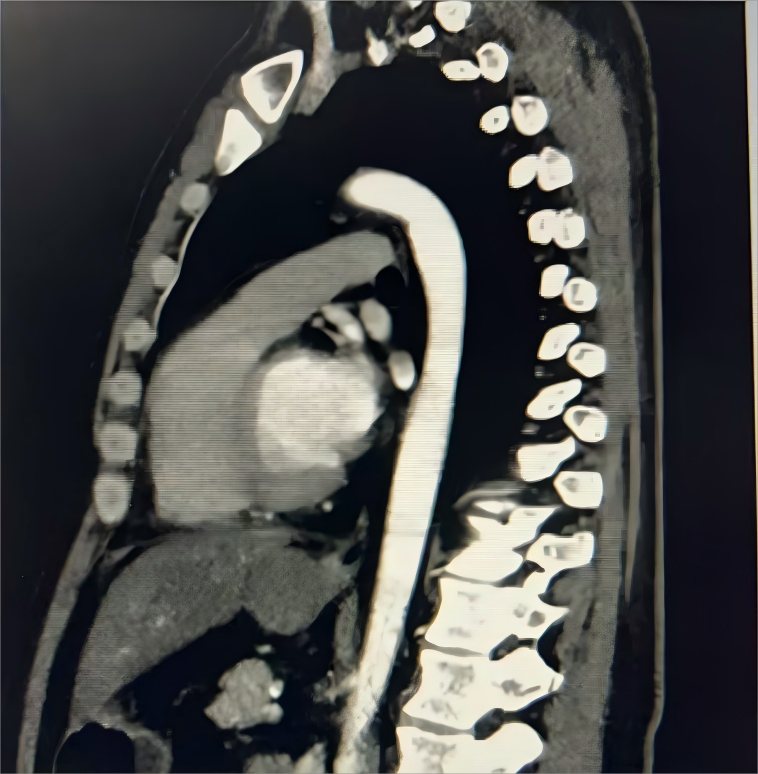

半月余前,患者吴先生于外院体检时发现食管下段肿物,虽无吞咽困难等症状,为求进一步诊治,经人介绍来到西安市第三医院。经消化内镜中心胃镜检查,考虑为食管良性肿瘤,随后转入胸外科接受治疗。

据该院胸外科主任杨锋介绍,食管良性肿瘤在食管肿瘤中仅占约1%,发病年龄较轻,症状进展缓慢。对于肿瘤较小、无明显临床症状的患者可暂时观察,但若肿瘤来源于肌层,则建议手术治疗。手术需精准把握解剖层次,避免损伤黏膜,降低术后并发症风险。

经全面评估并与消化内科专家共同讨论,一致认为患者手术指征明确,决定行腔镜辅助食管肿物切除术。术中,在麻醉科团队的全程护航下,消化内科专家通过胃镜精准定位肿瘤位置,胸外科手术团队精细操作,完整切除肿物并确认黏膜完好无损。